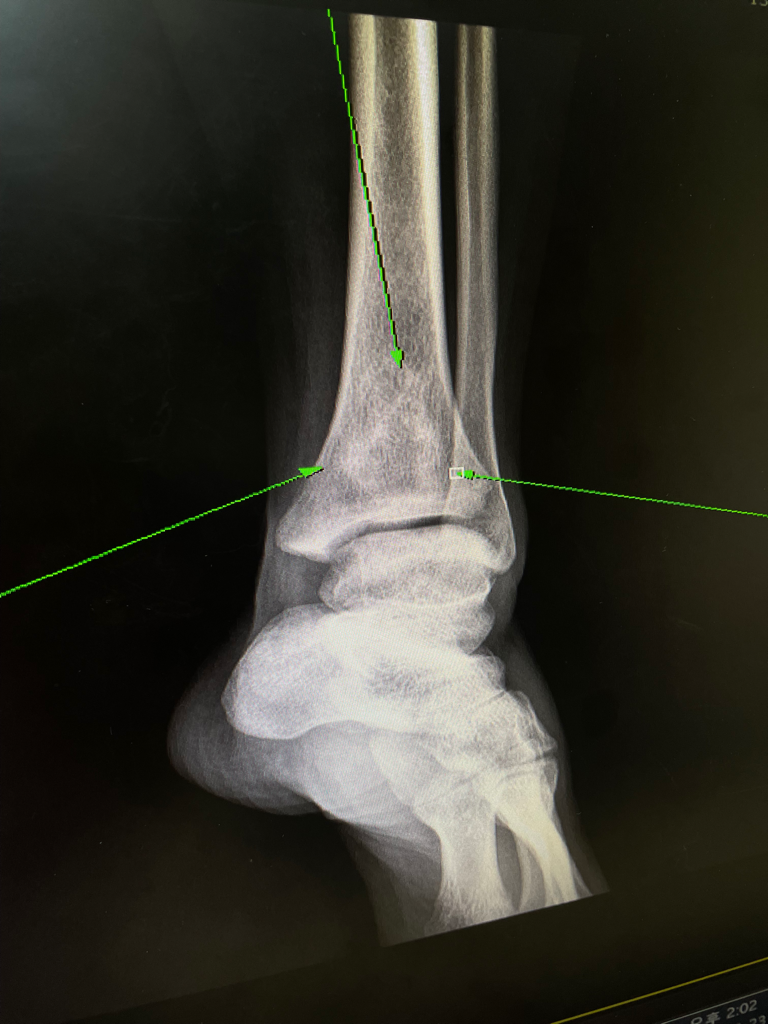

엑스레이 사진을 봐 주실 수 있나요? 대학 병원에 가야 하는지 궁금합니다.

지난 6월달에 생긴 발목 통증으로 인해 근처 동네 정형외과를 내원하여 엑스레이를 찍게 되었습니다.

뼈 안에 무언가가 있던 모습인데, 병원엔 좀 더 지켜봐도 된다고 하시며 대학병원을 추천하셨습니다.

• 1번 째 사진

• 해당 엑스레이 소견만으로는 알 수 있는 것이 많지 않습니다. 그렇기 때문에 더 정밀하게 파악하기 위해 MRI 검사를 권유하였을 것입니다. 증상이 지속된다면 문제가 있는 것을 의심해보아야 하며 현재까지 정보로는 명확하게 알 수 없기 때문에 대학병원에 가서 정밀한 검사를 통해서 정확한 감별 진단을 받는 것이 가장 먼저 필요해 보입니다.

골내부 종양의 가능성 까지 있기 때문에 현재 통증이 있으시다면 발목 MRI부터 촬영을 하시어 내부 상태를 확인해 보시고 정확한 진단이 나올시 전신 질환에 대한 감별을 해보시는 것이 좋겠습니다.